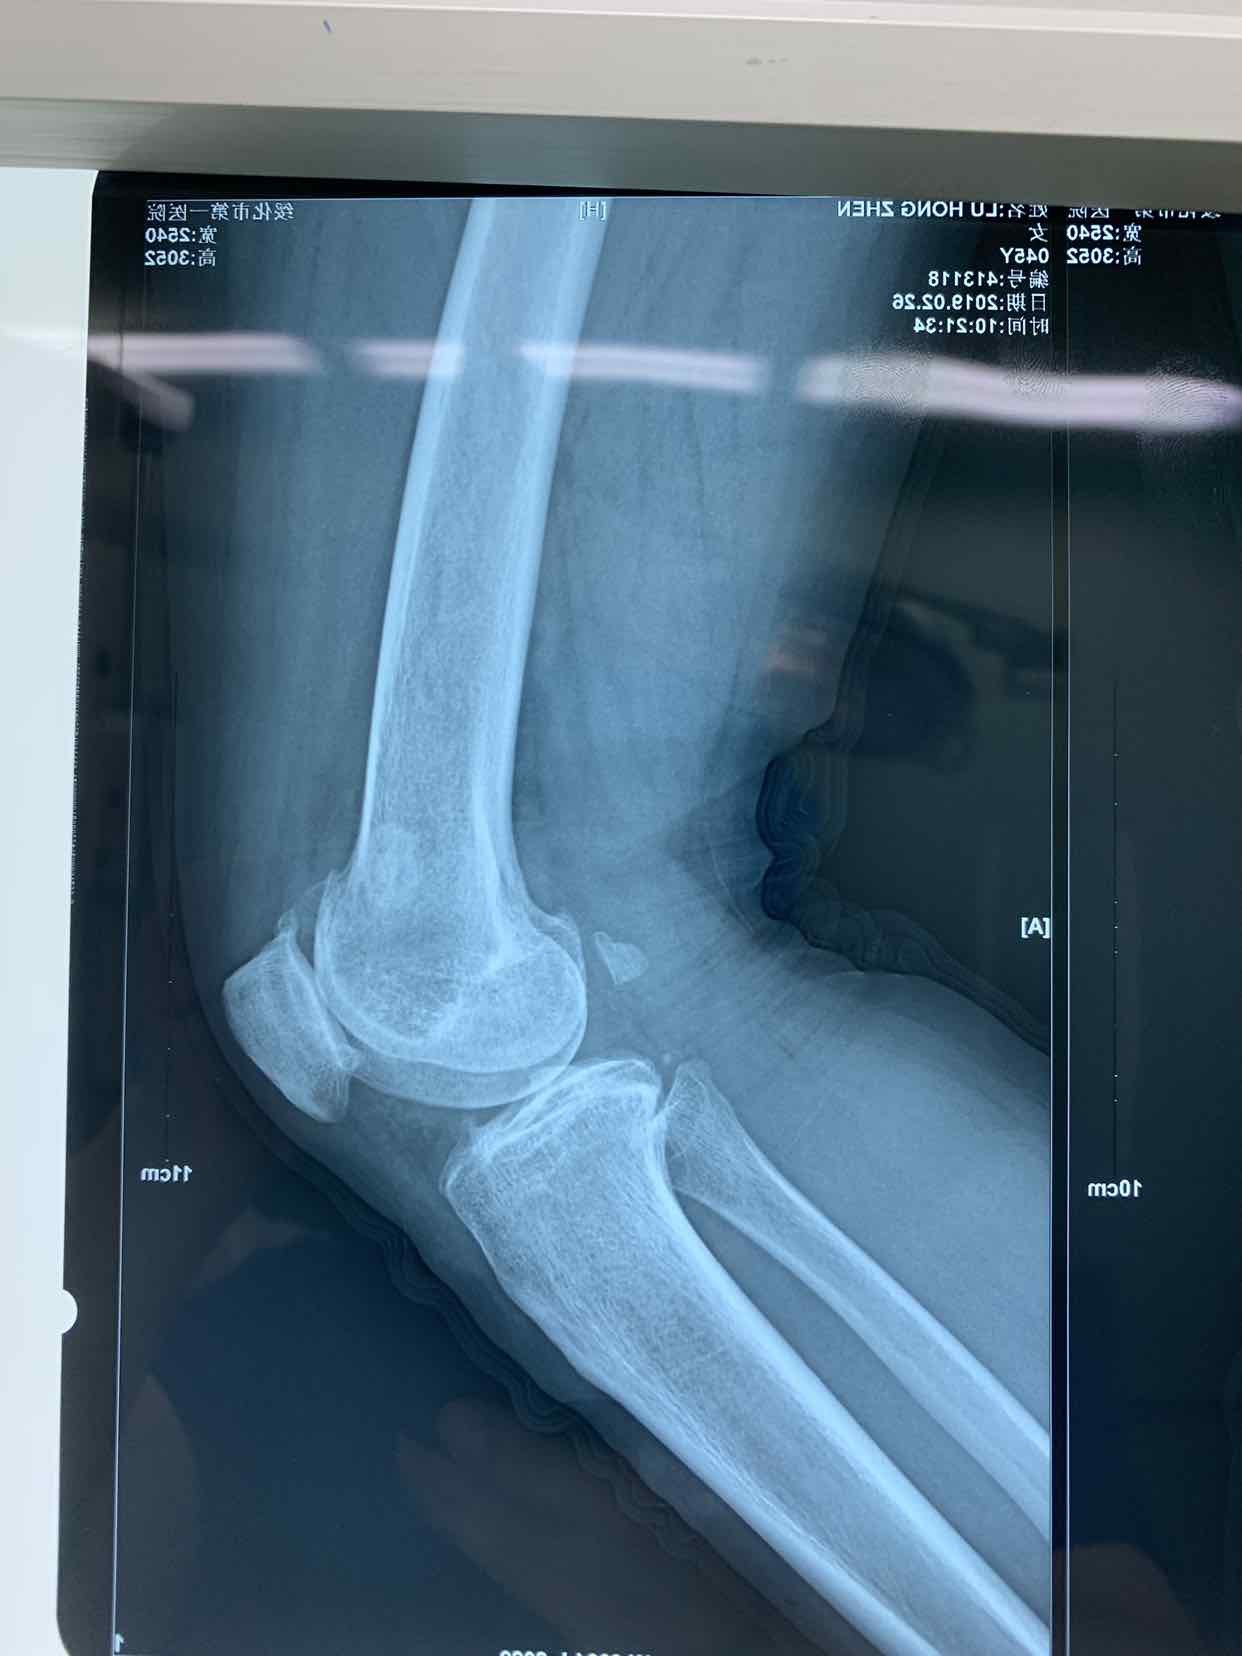

患者因双侧膝关节骨性肿物发现二十余年。收入院。患者无二十余年前无明显诱因发现双侧膝关节内有骨性肿物。异常活动。偶尔在屈曲活动时出现局部嵌夹于关节内。疼痛。不能活动。并弹响。近半年内肿物增大。疼痛发作频繁。遂来诊。门诊拍片提示见双侧膝关节内骨性游离体,位于关节内。门诊以双侧膝关节游离体收入院。

查体见患者双侧膝关节局部肿胀。压痛。可于局部触及骨性肿物在关节内游走。屈伸活动时偶有嵌顿。行走活动受限。拍片提示双侧膝关节骨性游离体。

诊断为双侧膝关节游离体。再局麻下银行膝部游离体取出术。术后患者恢复良好。

膝关节游离体是临床常见疾病。可以通过关节镜探查发作。拍片或者核磁共振检查也可获得可靠诊断。处理非常简单。发现肿物挤压至一侧。切口就可以取出。